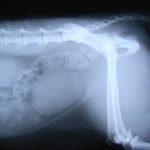

症例3:キルシュナーワイヤーのピンニングによる整復

ペルシャ猫 11ヶ月齢 雄

他院にて左大腿骨遠位の成長板骨折(salter-harrisⅠ型)が認められており、治療相談を目的として来院。当院にて、キルシュナーワイヤーを用いたピンニングにより骨折部位の整復を行いました。術後の経過は良好で、現在も経過観察中です。

術前レントゲン

術後レントゲン